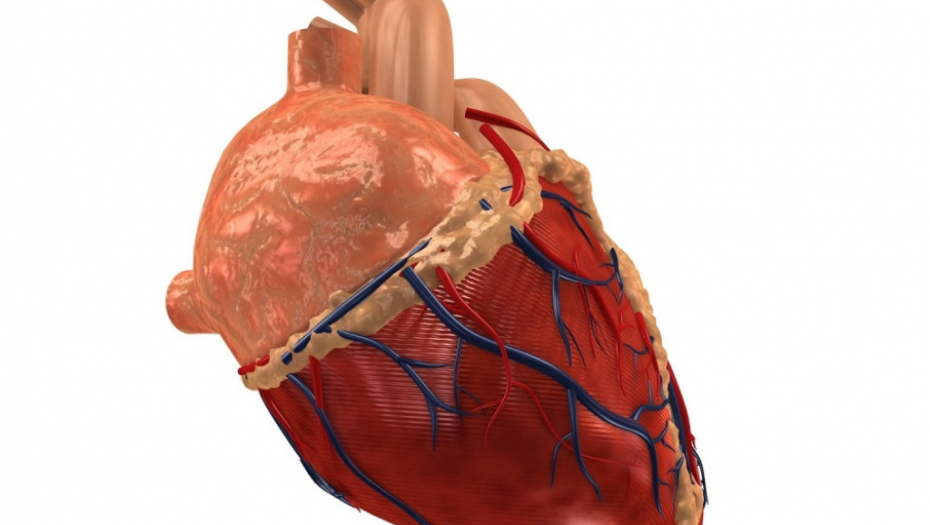

Shutterstock